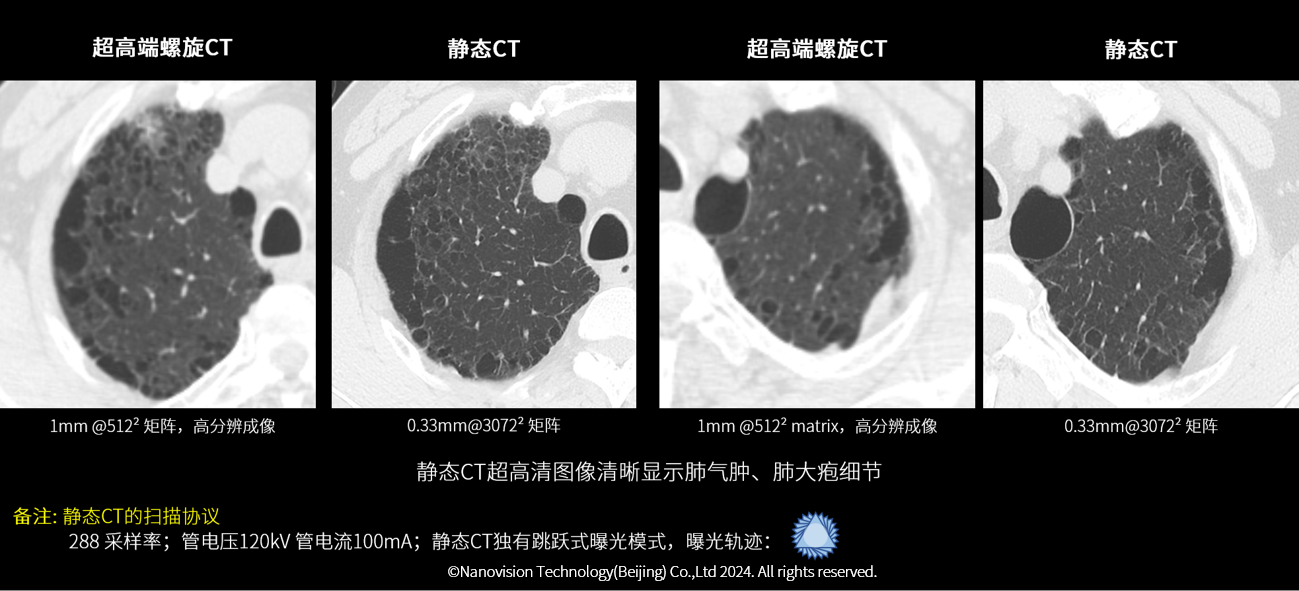

肺气肿患者随访成像比较